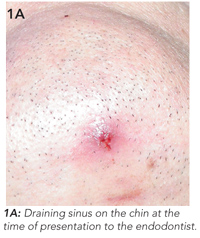

The patient had a history of a car accident which caused trauma to the teeth 15 years previously. He did not receive dental treatment at the time. Clinical examination revealed an erythematous lesion on the chin measuring 0.5 cm in diameter, from which pus drained freely (Figure 1A).